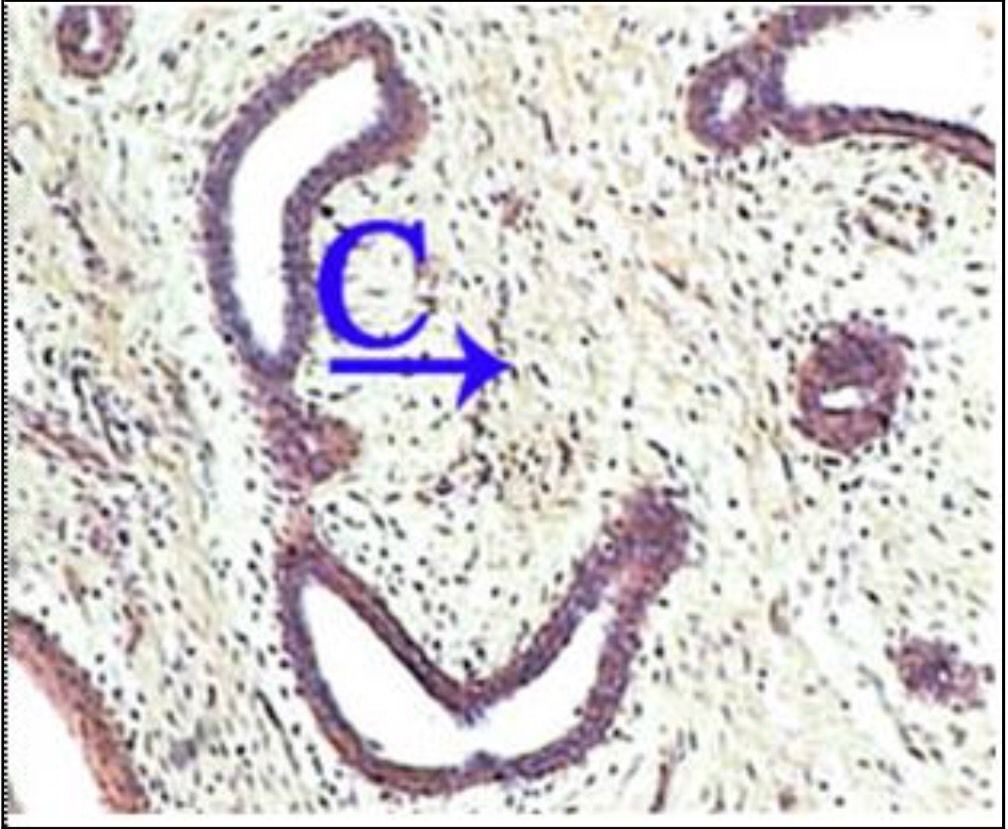

Question 107

Question

What is the correct answer at point A?

Answer

• - formation vasculaire de l’hémangiome

• - septa conjonctif

• - endothélium capillaire

• - globules rouges

• - lumière contenant de globules rouges

Question 108

What is the correct answer at point B?

Question 109

What is the correct answer at point C?

Question 110

What is the correct answer at point D?

Question 111

What is the correct answer at point E?